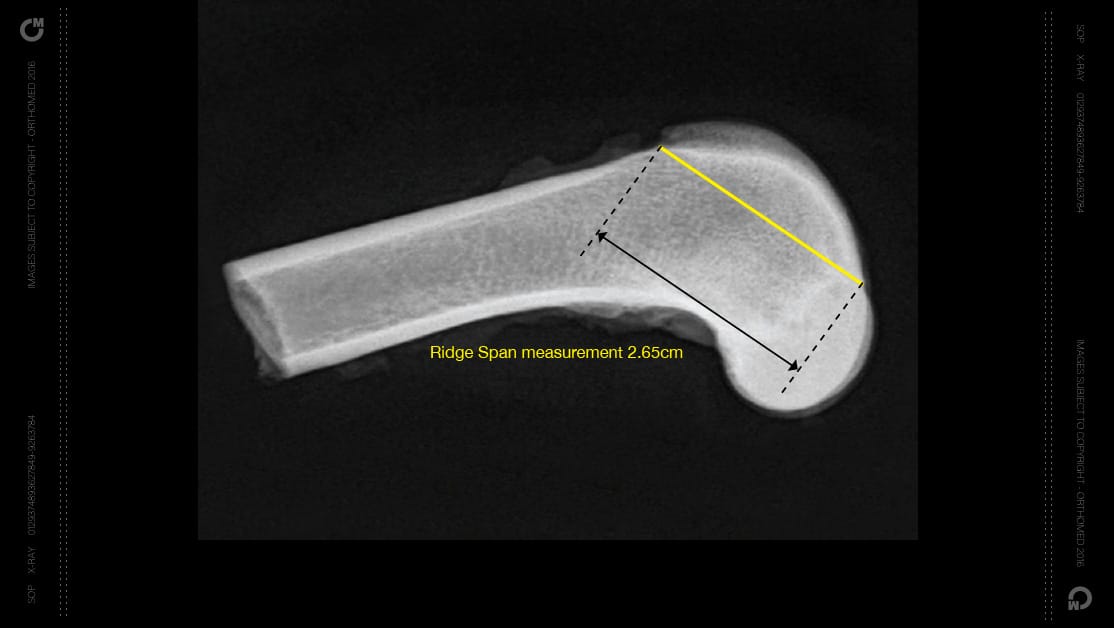

Available in five lengths, starting at a low profile 1.5cm up-to a 3.5cm, the RidgeStop™ implants cover most sizes of dogs (and some cats) for either a medial or lateral luxating patella. Determining the size of the implant required is from the Ridgespan measurement, taken from a standard lateral radiograph, measuring from the proximal extent of the trochlear ridge to the condylar notch.

Ridgespan drill guides to ensure the correct positioning during surgery

Each implant size has a corresponding drill guide, to ensure ideal placement of the implant. Depending on the implant size, they will require either two or three standard cortical bone screws, and the use of the drill guide allows not only ideal placement of the implant but also alignment of the divergent screw holes.